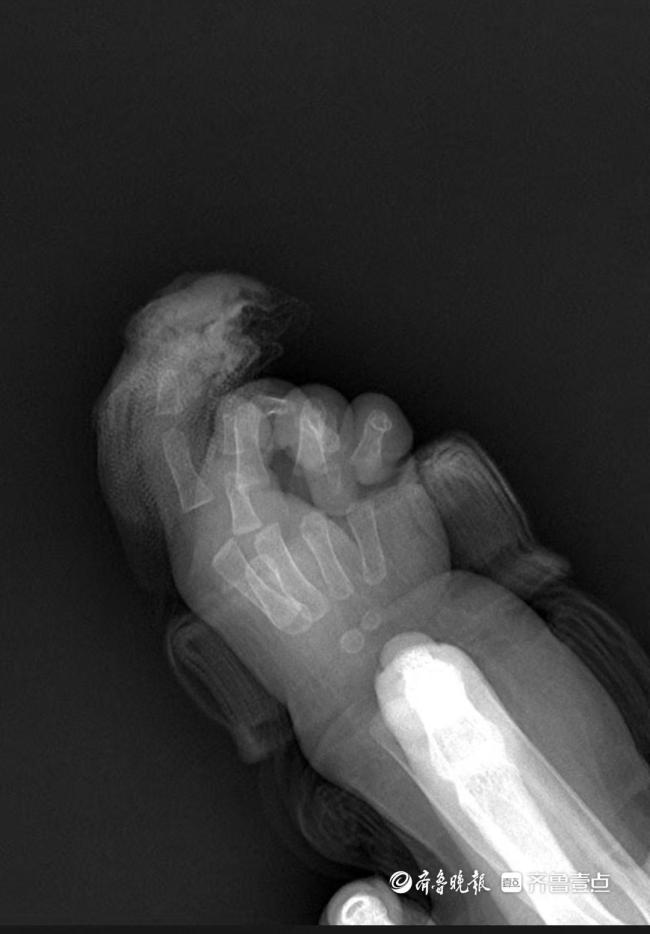

急诊就诊时间是9时22分,同步启动术前准备。手及上肢外科主治医生王思月回忆,急诊团队第一时间为芙芙止血、抽血、做心电图和拍片,“孩子伤口还在渗血,更换了3次纱布,同时输液,避免脱水。”